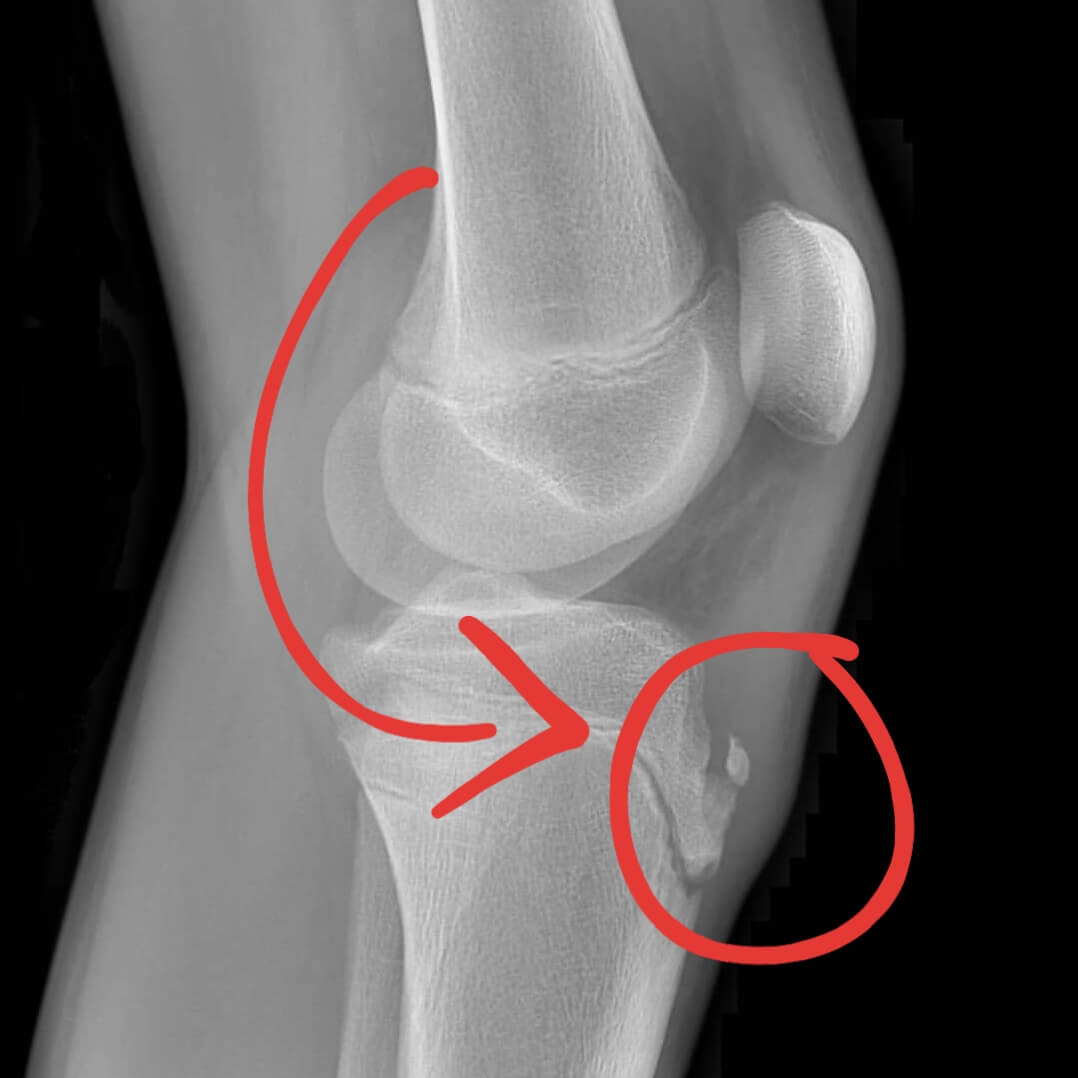

First described by surgeons Robert Osgood and Carl Schlatter in 1903, Osgood-Schlatter Disease involves irritation at the point where the patellar tendon attaches to the tibial tuberosity - the bony bump at the top of the shinbone.

This condition is classified as a traction apophysitis, meaning it results from repeated pulling forces on a growth plate. During adolescence, the tibial tuberosity consists of softer, developing cartilage rather than solid bone, making it more vulnerable to stress.

- Pain and tenderness at the front of the knee, specifically at the tibial tuberosity

- Visible bony bump at the top of the shin

Diagnosis is typically straightforward through physical examination, where pressure on the tibial tuberosity reproduces pain. Healthcare providers may ask patients to demonstrate movements like walking, jumping, or kneeling to assess discomfort levels.